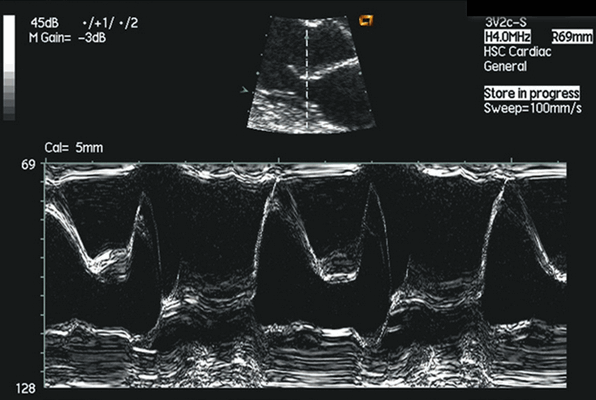

Митральный клапан в М-режиме на эхокардиографии

На эхокардиографии митральный клапан - одна из самых простых для распознавания структур сердца. В М-режиме митральный клапан имеет наибольшую амплитуду и ход, и его, несомненно, можно распознать по его «двойному» или двухфазному движению. Это движение в виде буквы М передней створки и W задней створки, вызывается открытием клапана в начале желудочковой диастоле при пассивном наполнении желудочка и активным сокращением предсердий в конце диастолы.

Когда начинается диастола, передняя створка митрального клапана выполняет быстрое движение вперед, достигая пика в точке «е». В то время как желудочек быстро наполняется кровью из левого предсердия, клапан закрывается в точке «f». Скорость, с которой происходит это движение, представляет собой скорость опорожнения левого предсердия и служит важным индикатором измененной митральной функции.

Когда левое предсердие сокращается, митральный клапан открывается при более коротком переднем движении и заканчивается в точке «а», которая возникает сразу после зубца P на электрокардиограмме. За этим движением следует быстрое движение назад от точки «b» к точке «c», которое совпадает с систолическим компонентом QRS на электрокардиограмме, вызванной сокращением левого желудочка, закрывающим клапан.